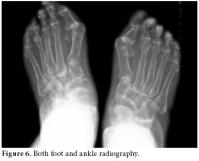

In foot-ankle X-rays, periarticular osteoporosis, hallux valgus, and joint space narrowing had progressed to the ankylosis of tarsal bones (figure 6).